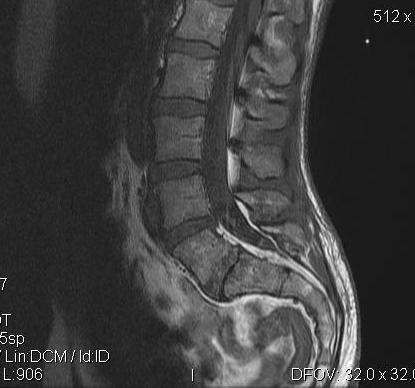

MRI

Disc

Normal disc / bright T2 signal

Degenerative disc / dark T2

Very sensitive

- 30% of asymptomatic patients < 60 years have abnormality

- 60% > 60 years have abnormality

Modic End Plate Changes

Classification of bone marrow changes in bone marrow adjacent to vertebral end plates

Type 1: High on T2 / Low on T1

Type 2: High on T2 / High on T1 (lipid changes)

Type 3: Low on T2 and T1 (sclerotic)